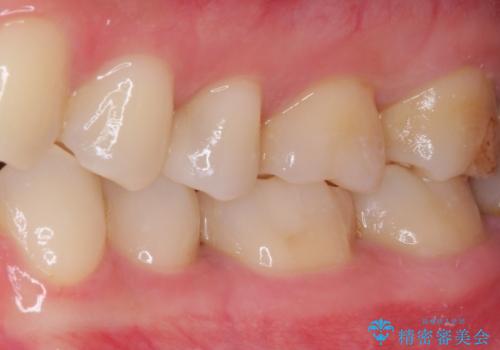

そして次の来院時、セラミックインレーを装着し、噛み合わせなどの調整を行います。

自然な色調で大変満足されました。